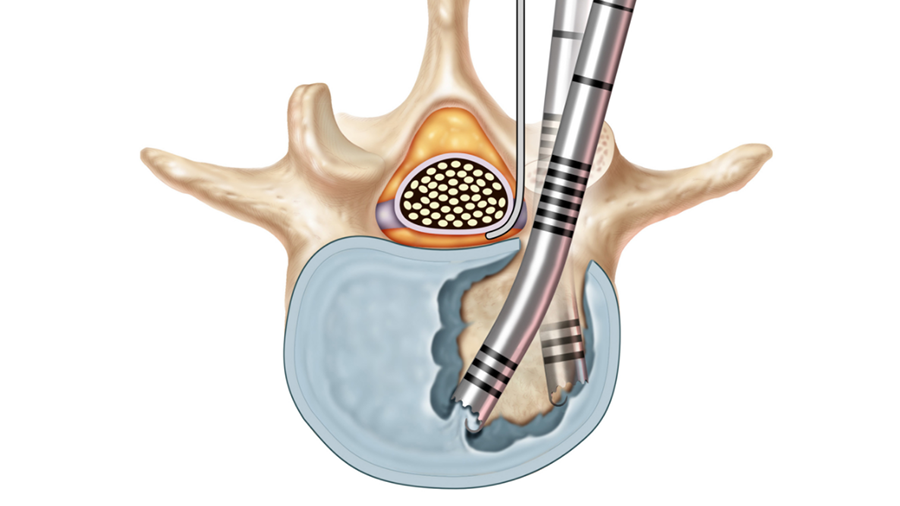

First, a C7/Th1 anterior cervical decompression and fusion was performed via a left-sided approach. After decompression of the spinal canal and bilateral neuroforaminal decompression of the C8 nerve route, stabilization was achieved with a stand-alone Syncage-C (DPS) that already significantly reduced the spondylolisthesis.

Second, a posterior revision surgery was performed including implant removal of the posterior instrumentation between C2 and C4 followed by a laminectomy of C7 with bilateral foraminotomy of the C8 nerve routes. Re-instrumentation with isthmic screws at the level C2, lateral mass screws at the level C4, C5, and C6, as well as bilateral pedicle screws at the level T2 and T3 were performed using the new Symphony system (DPS). The Symphony system offered the opportunity to place 4.0 mm screws in the previous loosened screw location at the level C2. The 3.5 mm screws were placed in C4, C5, and C6, and 5.5 and 5.0 mm screws at T2 and T3, respectively. The 4.0 mm rod allowed a good direct connection between the cervical spine isthmic and lateral mass screws and the thoracic pedicle screws, providing adequate stability and allowing excellent reduction. An intraoperative image is shown in Fig 3. Postoperative radiographic evaluations are displayed in Fig 4.